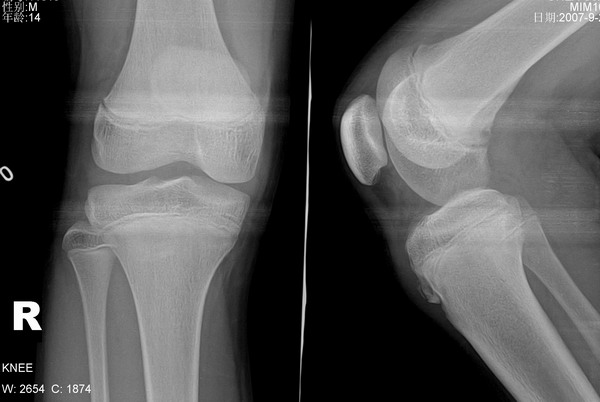

胫骨结节 男 14岁 平时常参加体育活动 右侧胫骨结节处按压或活动时疼痛.

本病1、发病年龄

2、膑韧带下端增厚肿胀

3、胫骨结节骨骺前缘见骨质缺损

4、胫骨结节前方断续钙化

5、局部疼痛

6、非滑膜部位

均支持胫骨结节骨软骨病(奥许氏病)以上为个人意见,仅供参考。